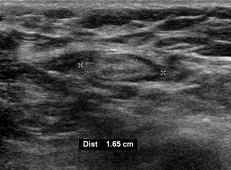

의료 초음파에서 B-모드 영상은 림프절 형태를 보여주며, 파워 도플러는 혈관 패턴을 평가할 수 있다.[28] 전이와 림프종을 구별할 수 있는 B-모드 영상 특징에는 크기, 모양, 석회화, 힐룸 구조의 소실, 림프절 내 괴사가 포함된다.[28] 연조직 부종과 B-모드 영상에서 림프절 유착은 결핵성 경부 림프절염 또는 이전 방사선 치료를 시사한다.[28] 림프절 크기와 혈관의 일련의 모니터링은 치료 반응을 평가하는 데 유용하다.[28]

의료 초음파에서 B-모드 영상은 림프절 형태를 보여주며, 파워 도플러는 혈관 패턴을 평가할 수 있다.[28] 전이와 림프종을 구별할 수 있는 B-모드 영상 특징에는 크기, 모양, 석회화, 힐룸 구조의 소실, 림프절 내 괴사가 포함된다.[28] 연조직 부종과 B-모드 영상에서 림프절 유착은 결핵성 경부 림프절염 또는 이전 방사선 치료를 시사한다.[28] 림프절 크기와 혈관을 일련으로 모니터링하는 것은 치료 반응을 평가하는 데 유용하다.[28]